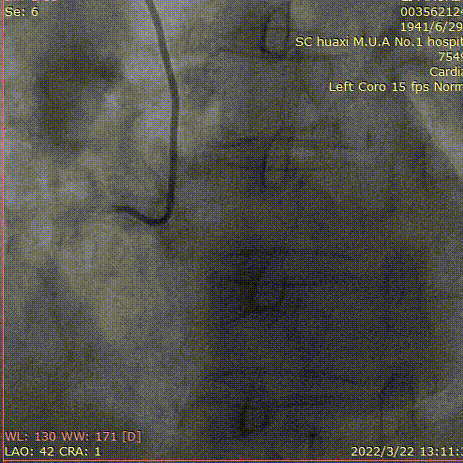

造影说明:前降支开口重度狭窄,近段闭塞,入口不清,闭塞段长,走形不清。自身可见桥侧支形成,远端血管细小。